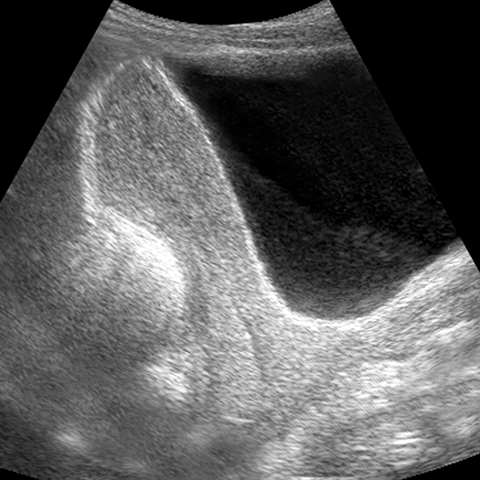

Anteverted uterus, ultrasound [4 of 4]